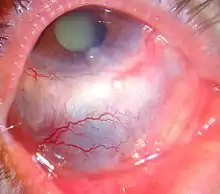

Scleritis is a serious inflammatory disease that affects the white outer coating of the eye, known as the sclera. The disease is often contracted through association with other diseases of the body, such as granulomatosis with polyangiitis or rheumatoid arthritis. There are three types of scleritis: diffuse scleritis (the most common), nodular scleritis, and necrotizing scleritis (the most severe). Scleritis may be the first symptom of onset of connective tissue disease.[1]

- Redness of the sclera and conjunctiva, sometimes changing to a purple hue

The pain of episcleritis is less severe than in scleritis.[4] In hyperemia, there is a visible increase in the blood flow to the sclera (hyperaemia), which accounts for the redness of the eye. Unlike in conjunctivitis, this redness will not move with gentle pressure to the conjunctiva.

Scleritis is best detected by examining the sclera in daylight; retracting the lids helps determine the extent of involvement. Other aspects of the eye exam (i.e. visual acuity testing, slit lamp examination, etc.) may be normal. Scleritis may be differentiated from episcleritis by using phenylephrine eye drops, which causes blanching of the blood vessels in episcleritis, but not in scleritis.[4]

Scleritis can be classified as anterior scleritis and posterior scleritis. Anterior scleritis is the most common variety, accounting for about 98% of the cases. It is of two types : Non-necrotising and necrotising. Non-necrotising scleritis is the most common, and is further classified into diffuse and nodular type based on morphology. Necrotising scleritis accounts for 13% of the cases. It can occur with or without inflammation.